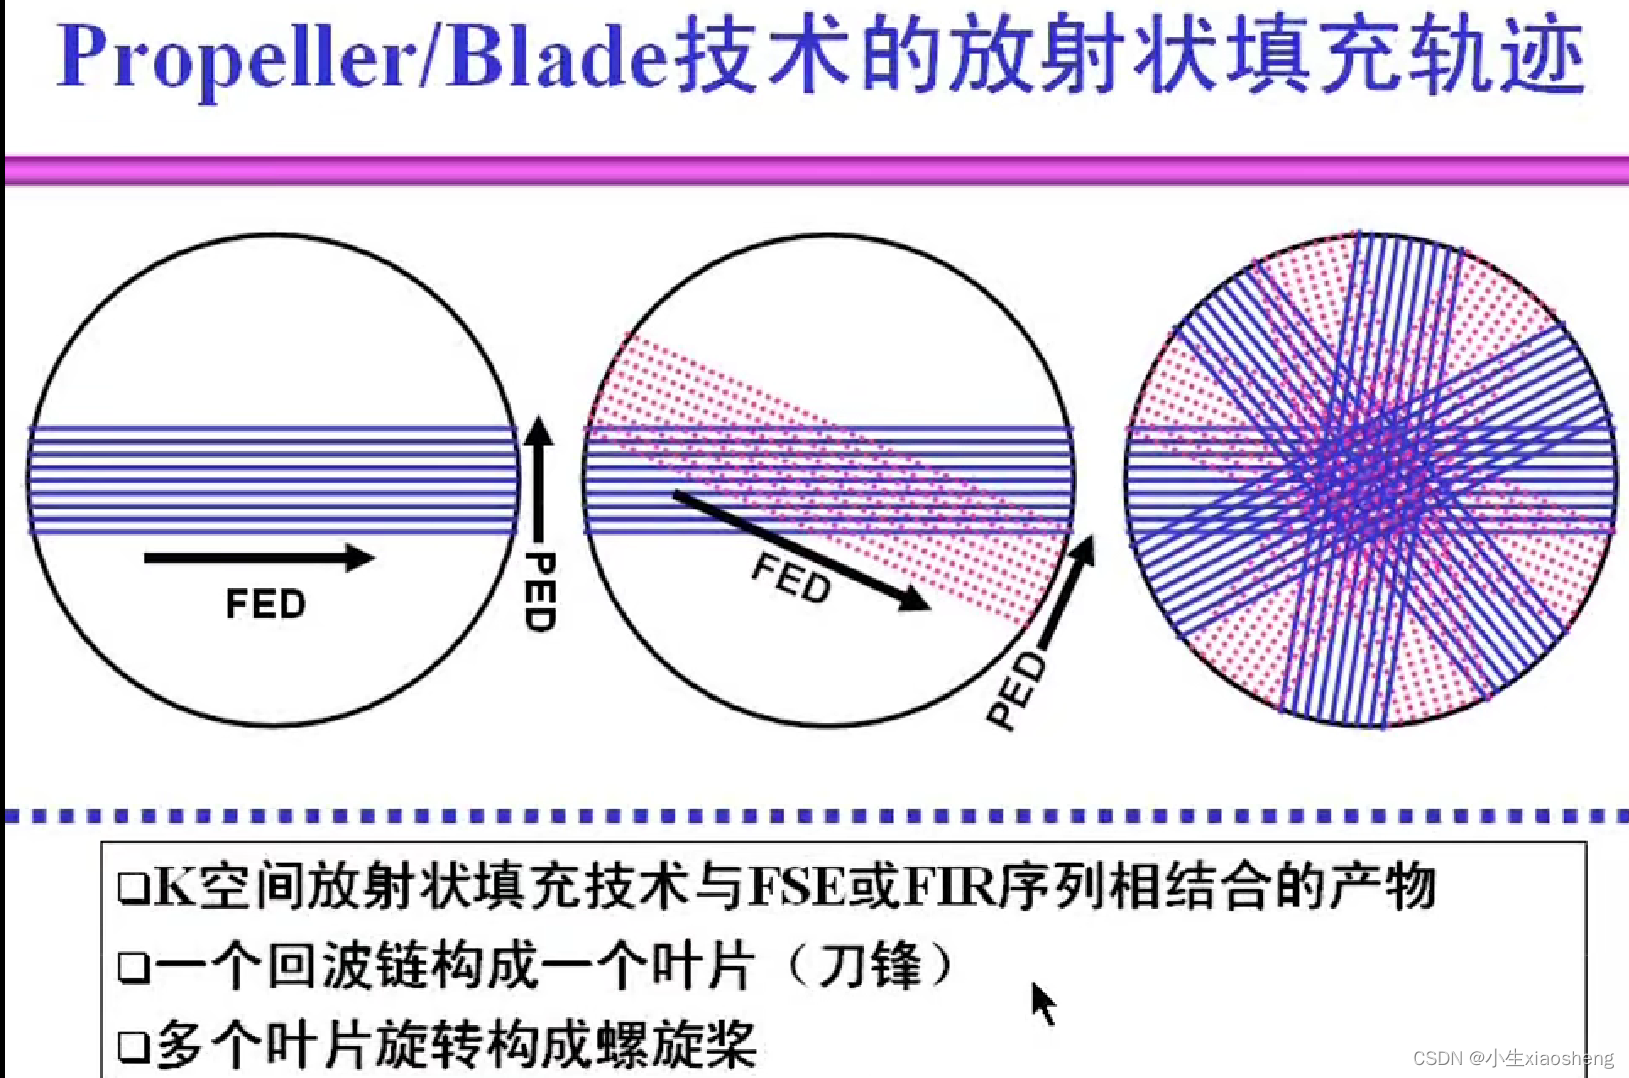

六、Propeller/Blade序列

螺旋桨和刀锋序列,其实也就是常规FSE(快速自旋)或IR-FSE(反转恢复)序列的K空间填充,可以和其他技术结合来减少运动伪影。

自旋回波--90度和180度填充K空间;反转恢复--在自旋的基础上两边加180度;梯度回波--消除每次脉冲留下的影响,以及波的次数;propeller==》K空间填充技术和FSE或FIR结合用于减少运行伪影;EPI==》采集方式,一次激发采集多个回波的形式但与单次不一样;PRESTO和GRASE==》前面几种的一种结合形成新的。